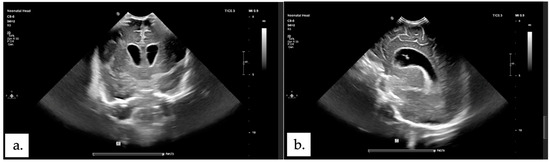

2.1. Patient 1